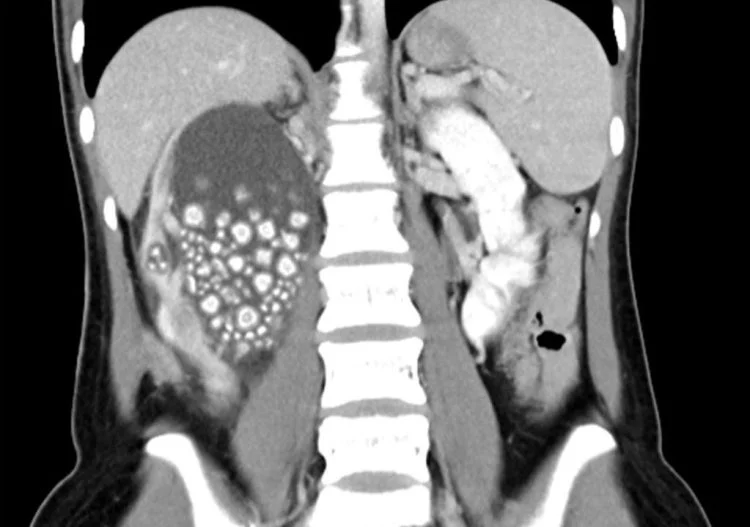

Μία 20χρονη παραπονιόταν για έντονο πόνο στο κάτω μέρος της πλάτης της και οι γιατροί που την εξέτασαν, βρήκαν 300 μικρές πέτρες στο νεφρό της.

Ειδικότερα, η γυναίκα από την Ταϊβάν υποβλήθηκε πρόσφατα σε χειρουργική επέμβαση, προκειμένου να αφαιρεθούν 300 μικροί λίθοι από το δεξί της νεφρό.

Μετά την αξονική τομογραφία, διαπιστώθηκε ότι το δεξί νεφρό της Yu ήταν γεμάτο πέτρες και η πρώτη ενέργειά των γιατρών ήταν να χορηγηθούν στη νεαρή γυναίκα αντιβιοτικά, ενώ στη συνέχεια αφαίρεσαν του εκατοντάδες λίθους.

Τελικά, οι γιατροί αφαίρεσαν πάνω από 300 πέτρες, μεγέθους μεταξύ 5 και 2 εκατοστών, με την ασθενή να τους ενημερώνει ότι δεν έπινε σχεδόν καθόλου νερό και προτιμούσε τα ζαχαρούχα τσάγια και χυμούς για ενυδάτωση, με αποτέλεσμα αυτό της προκάλεσε χρόνια αφυδάτωση.